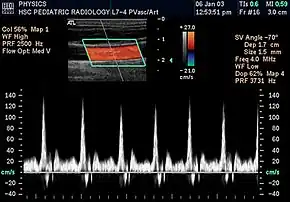

Spectral duplex scan of the common carotid artery | |

Doppler ultrasonography is medical ultrasonography that employs the Doppler effect to perform imaging of the movement of tissues and body fluids (usually blood),[1][2] and their relative velocity to the probe. By calculating the frequency shift of a particular sample volume, for example, flow in an artery or a jet of blood flow over a heart valve, its speed and direction can be determined and visualized.

Duplex ultrasonography sometimes refers to Doppler ultrasonography or spectral Doppler ultrasonography.[3] Doppler ultrasonography consists of two components: brightness mode (B-mode) showing anatomy of the organs, and Doppler mode (showing blood flow) superimposed on the B-mode. Meanwhile, spectral Doppler ultrasonography consists of three components: B-mode, Doppler mode, and spectral waveform displayed at the lower half of the image. Therefore, "duplex ultrasonography" is a misnomer for spectral Doppler ultrasonography, and more exact name should be "triplex ultrasonography".[3]

Colour Doppler shows the direction of the blood flow in red or blue (either towards or away from the transducer). Meanwhile, spectral Doppler not only shows the direction of blood flow, it also shows the phases (pulsatility) and acceleration of the blood flow. Any sudden changes in direction of blood flow produces audible sounds on the ultrasound machine.[3]

In spectral Doppler, the y-axis shows the direction and velocity of the flow. Meanwhile, the x-axis (as known as "baseline") shows the flow over time. The gradient at any point on the waveform would therefore shows the acceleration of the flow. In "antegrade" flow, the blood flows according to the normal flow within the circulatory system (e.g. veins flow towards the heart while arteries flows away from the heart). In "retrograde" flow, the flow would reverse (e.g. veins flow away from heart or arteries flow towards the heart). However, "retrograde" flow can be both abnormal or normal. For example, in portal hypertension, there is an abnormal portal venous flow where it flows away from the liver (hepatofugal flow) instead of the normal flow towards liver (hepatopetal flow). In jugular venous pressure waveform of the internal jugular vein, the retrograde "a" waveform is a normal flow due to right atrium contraction. Both antegrade or retrograde flow can be either towards or away from the probe transducer, depending on the position of the probe relative to the blood flow. Blood flow toward the transducer would appear above the baseline while blood flows away from the transducer will appear below the baseline. Waveform of the flow can be classified as: pulsatile (as in arteries), phasic (as in veins), non-phasic (as in diseased veins), and aphasic (no flow). Spectral broadening (thickness of the waveform) increases from large vessels (plug flow) to medium vessels (laminar flow) to small/stenotic/diseased vessels (turbulent flow) due to a larger variety of blood with different ranges of velocities in those with turbulent flow.[3]